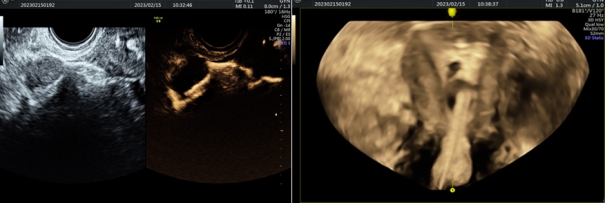

▲ 左侧输卵管通而不畅,右侧输卵管通畅

▲ 造影过程

四维超声子宫输卵管造影技术是在四维超声监视下,通过向宫腔注入造影剂,实时观察造影剂通过宫腔、输卵管时的流动及进入盆腔后的分布情况,可显示输卵管形态、输卵管积水、通畅情况、伞端是否与周围组织粘连,以判断输卵管的通畅性,同时还能观察子宫、卵巢及盆腔情况。